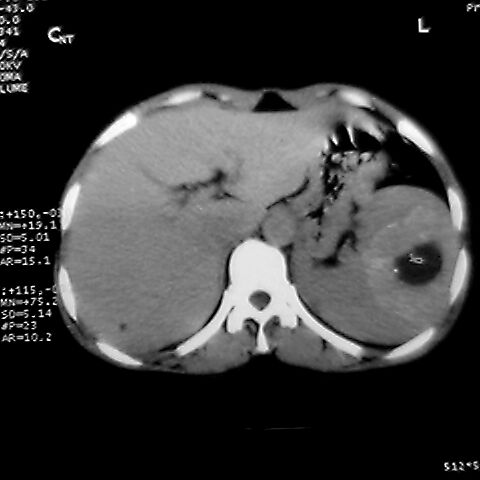

女 48岁 食道癌术前体检发现脾占位。

脾胀内部巨大低密度肿块,边界清或不清,中心坏死,轻度增强,内见散在钙化,结合食道癌病史多考虑:转移癌.

1肝右下叶小囊肿2右肾上极囊肿或错构瘤3脾脏不典型血管瘤可能性大.

脾脏低密度灶伴钙化,增强化明显,中心见液化坏死灶,强化延时明显。考虑血管瘤。转移瘤待排。